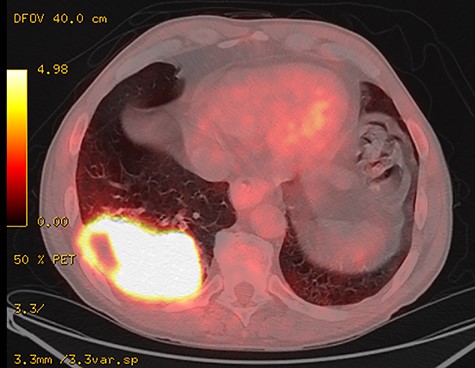

A 66-year-old male ex-smoker (60 pack years) with chronic obstructive pulmonary disease (COPD) Gold II was successfully treated for pneumonia. During his treatment, a suspicious lesion was detected in the right lower lobe. A positron emission tomography–computed tomography (CT) scan showed a highly hypermetabolic tumour with suspicion of chest wall infiltration. A transbronchial biopsy confirmed an adenocarcinoma of the lung (Fig. 1). There was no evidence for distant or mediastinal lymph node metastasis. Pulmonary function showed an Forced expiratory volume in 1 second (FEV1) of 78.1%, vital capacity (VC) of 117% and a diffusion capacity of the lung for carbon monoxide by the single breath (DLCO cSB) of 70.8% of predicted value. Further examinations including spiroergometry and single-photon-emission computed tomography–CT confirmed functional operability up to bilobectomy. There were no major associated comorbidities.

Positron emission tomography–CT scan of the primary tumour originating in the right inferior lobe and invading the adjacent thoracic wall.